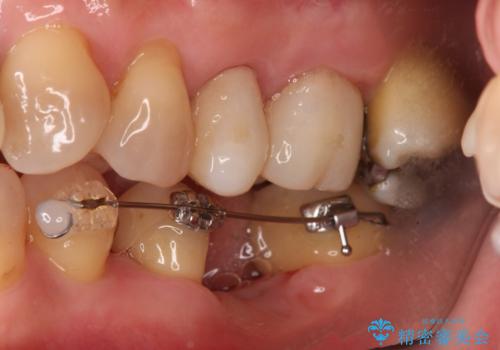

インプラントではなくブリッジにするためには、奥歯の並びを矯正しておいた方がいい状態でした。

抜歯後に部分的にワイヤー矯正を半年ほど行ってから、ブリッジを入れる治療を行いました。